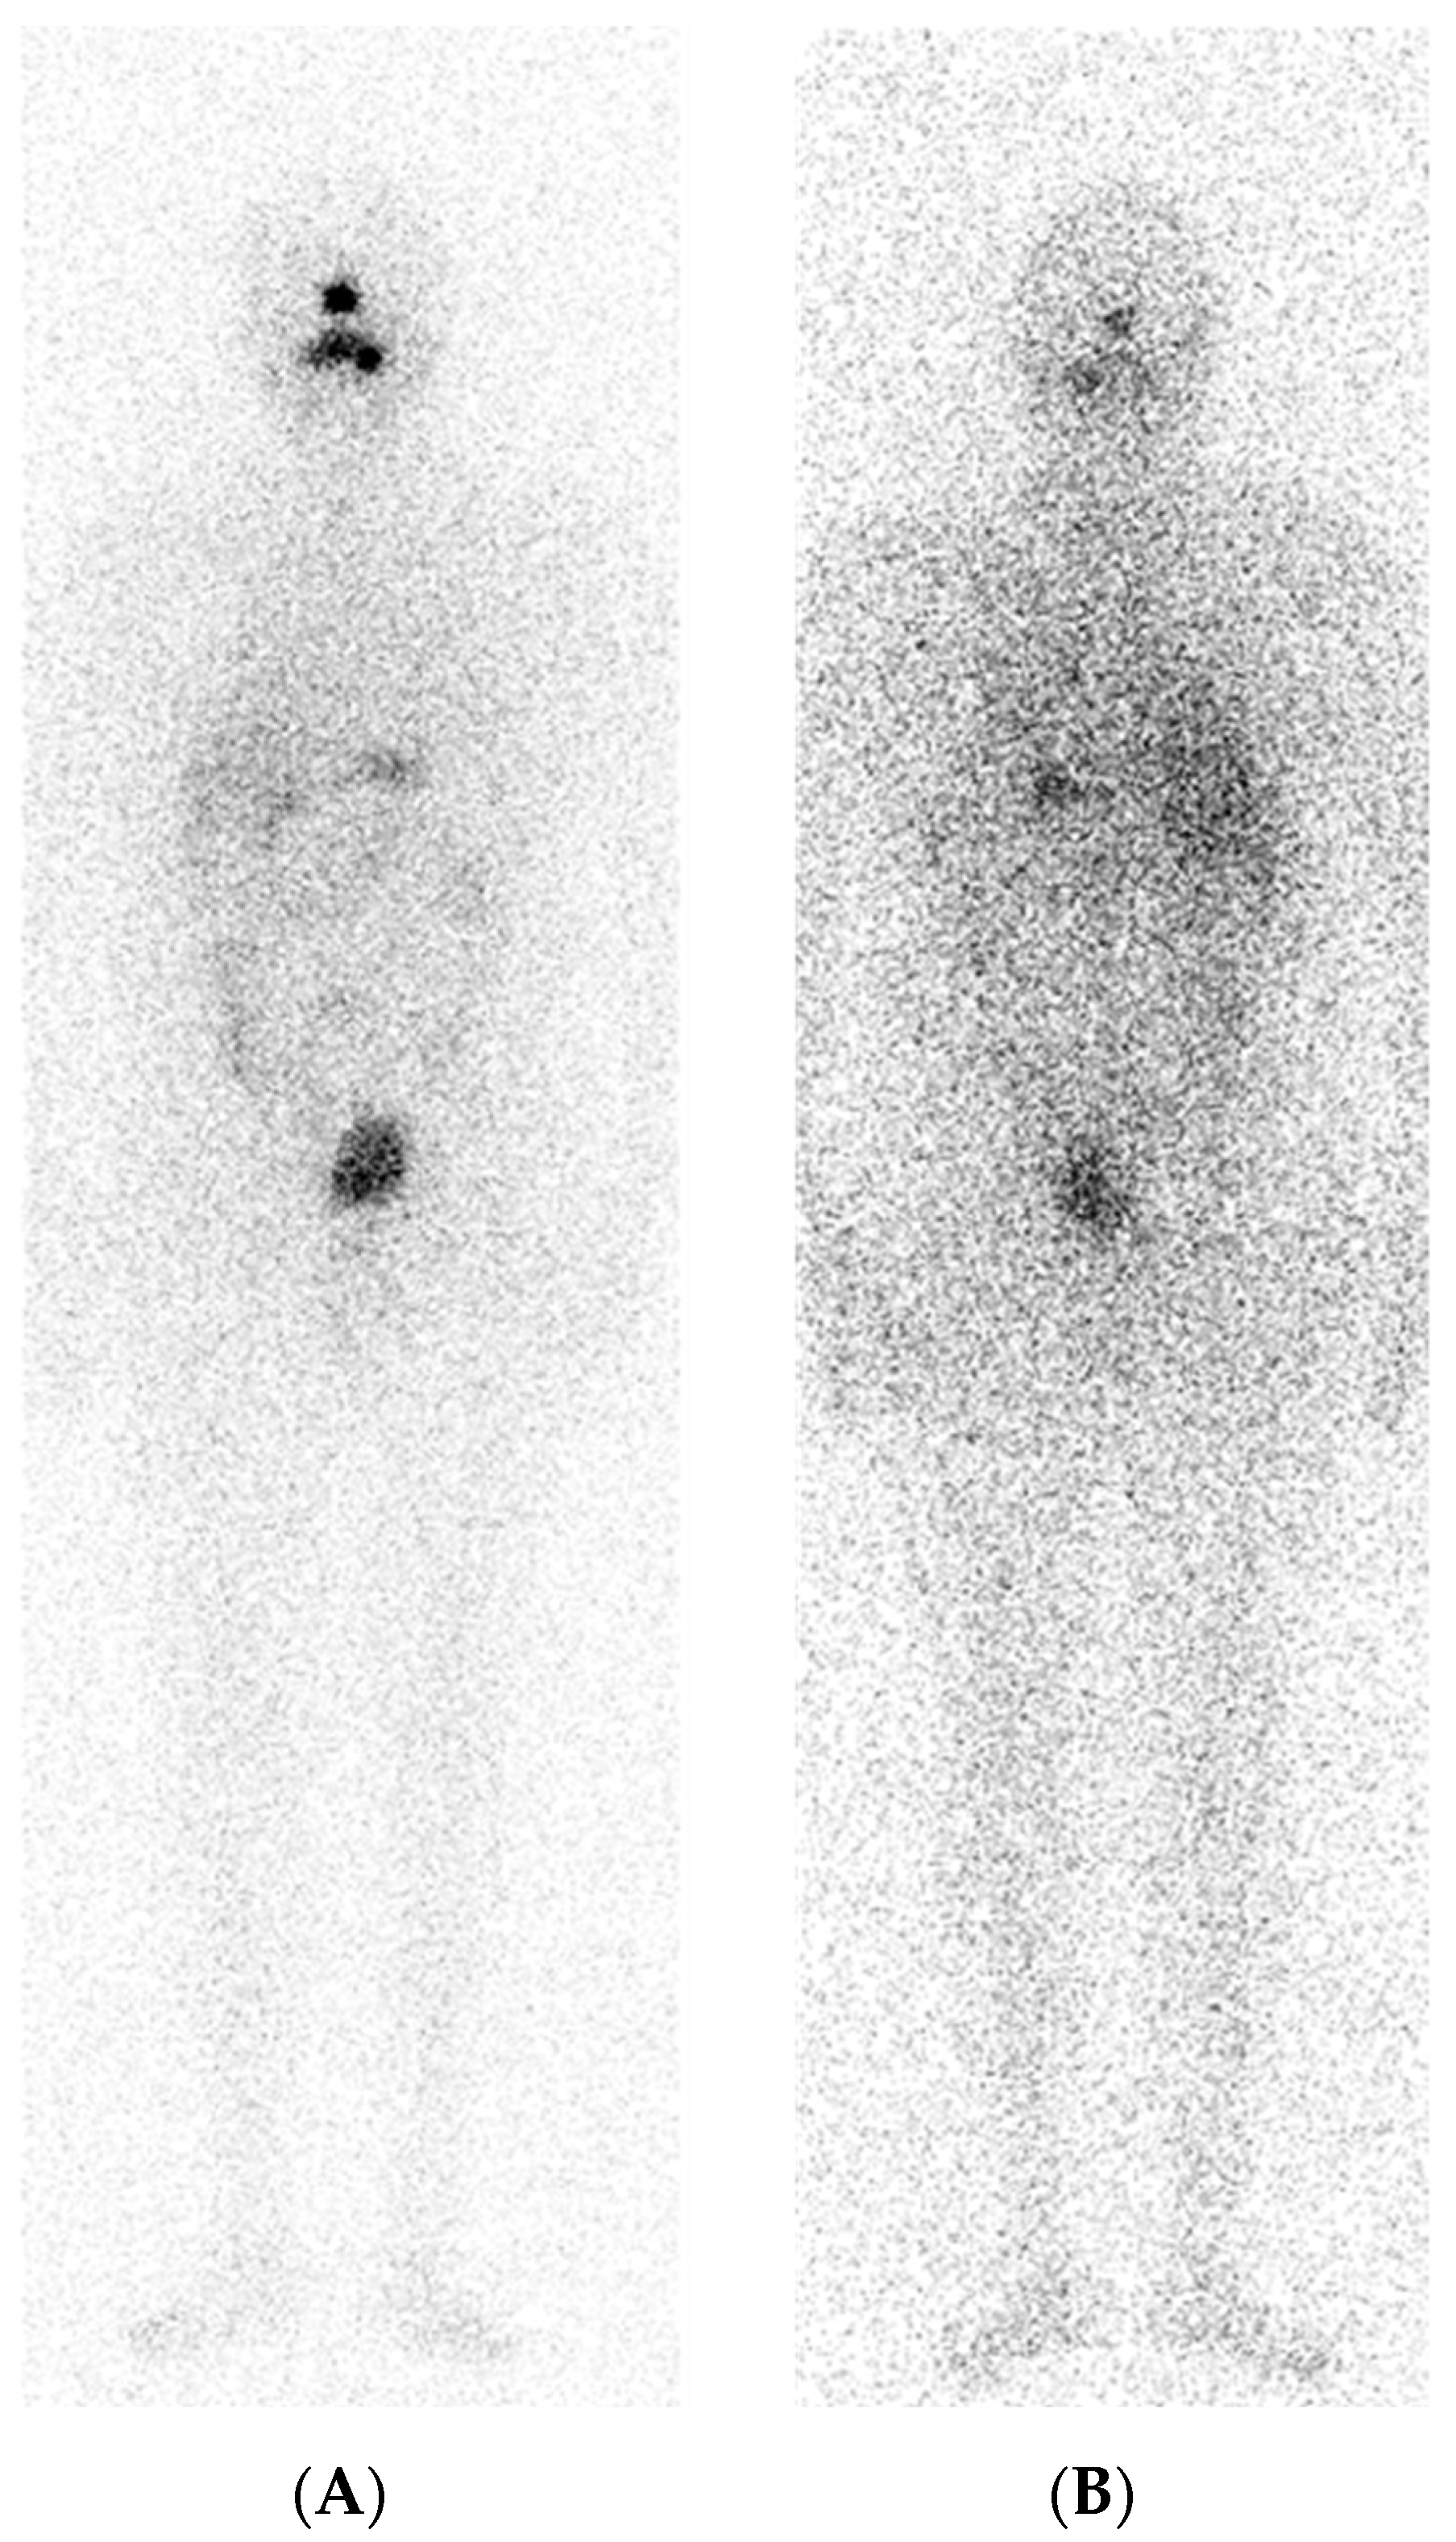

6. A Case of Re-Differentiation